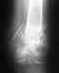

Было падение на плечо, головой вниз (в шлеме).После чего край ключицы торчит вверх, можно прижать обратно, но она возвращается в исходное положение - торчит. Болезненные ощущения только от гематомы при этом.

Ходил неделю в плотной повяке, сейчас сменили на косынку, и, в чем собственно вопрос, уверяя что через пару недель боль пройдет, а то что ключица торчит - это ни на что не влияет, просто не красиво. Можно сделать операцию в любое время, когда пройдет плечо (рукой больно шевелить).

Необходима немедленная операция и так ли все на самом деле как сказал местный доктор?

Операцию сделать можно и пораньше, и попозже. Есть неплохие шансы на приемлемый результат без операции. Если же результатом неоперативного лечения будет болезненная нестабильность, то и принять решение об операции.